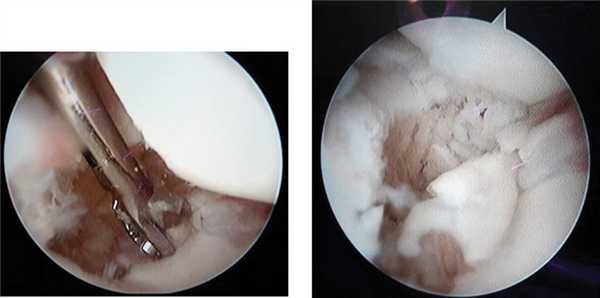

Через лучевой среднезапястный порт (ЛуСП) при помощи кусачек производили удаление рубцовой ткани, резекцию ложного сустава ладьевидной кости (рис. 3 а, Рис. 3. Дебридмент зоны ложного сустава (а); внешний вид ладьевидной кости после резекции ложного сустава (б). б).